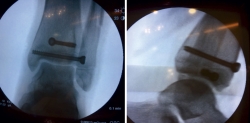

Bajo anestesia general se intentó la reducción cerrada de las fracturas, sin éxito (Figura 3).

Figura 3. Radiografía intraoperatoria después de reducción cerrada.